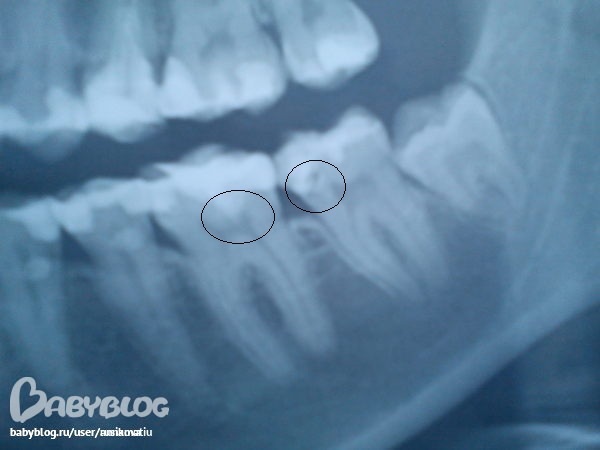

На 7 снизу справа зубе киста!!!! Сделайте прицельный рентгеновский снимок, если там такая же картина- перелечивать зуб обязательно.

В противном случае его можно потерять.

Горизонтальные стрелки указывают на возможный кариес на контактных поверхностях зуба.